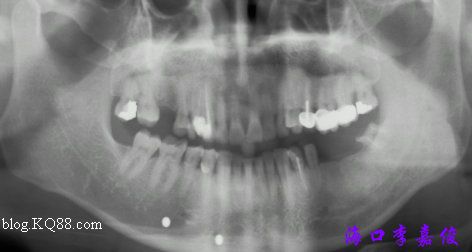

術(shù)前全景